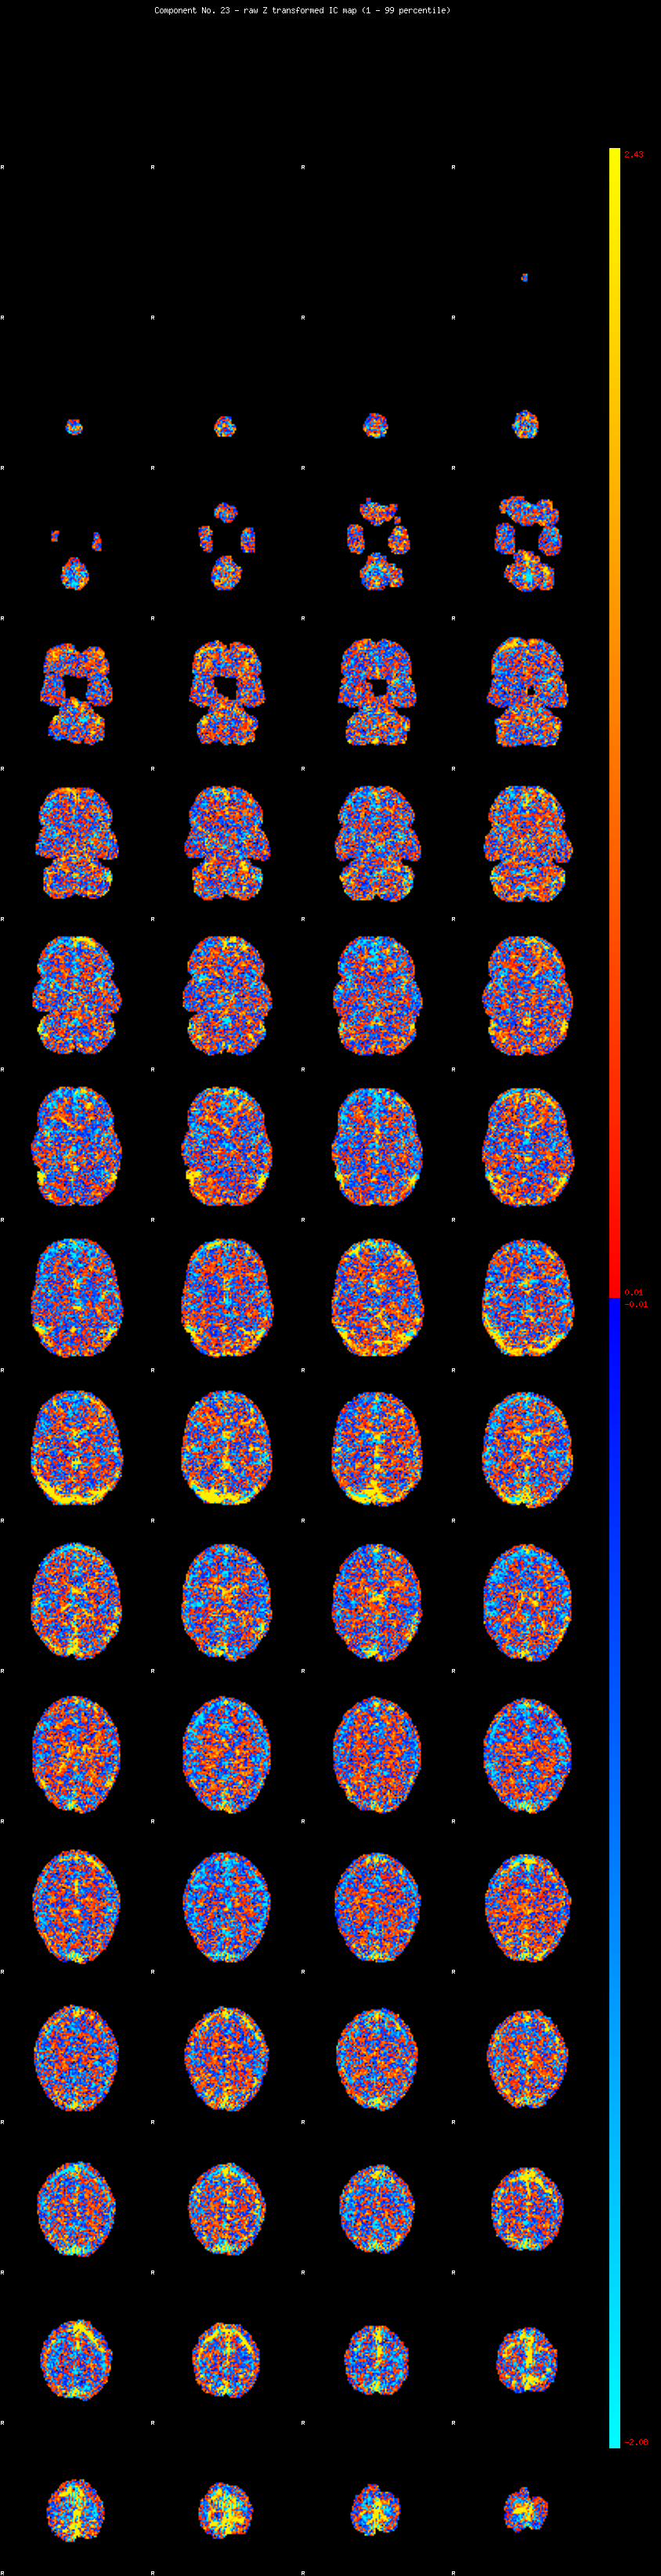

IC_23 Mixture Model fit

Means : -0.000000 3.696606 -2.490361

Vars : 1.000000 6.490062 2.057799

Prop. : 0.906548 0.052257 0.041195